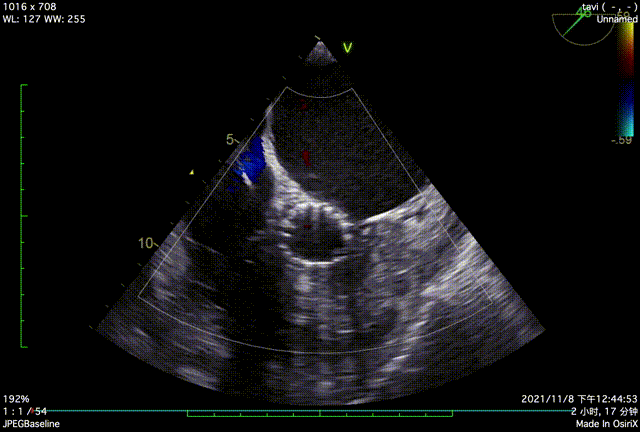

TTE入院

TTE